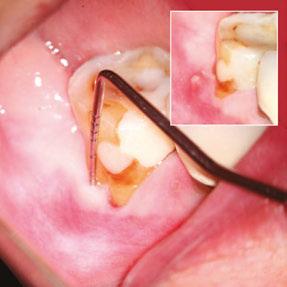

When the IRR is diagnosed, root canal treatment is the treatment of choice. The prognosis is, in general, very good except when the resorption has perforated the dentin wall connecting the root canal with the periodontium.3,4,8 In many cases, this communication can’t be observed radiographically. Before performing endodontic therapy, it is always important to evaluate if the tooth is deemed restorable and what kind of reconstruction is needed. Properly cleaning and shaping the area of resorption may be very challenging because in many cases, it presents a complex access.

Different strategies have been proposed for instrumentation, such as use of sonic and ultrasonic activation of sodium hypochlorite,9,10 activation with the XP-Endo® Finisher file10 (FKG, Dentaire SA, La Chaux de Fonds, Switzerland), the use of precurved files in the RDI area,11 multiple visits using calcium hydroxide as intracanal medication, and sodium hypochlorite as irrigant in order to improve the disinfection of areas that are difficult to access.3,4

In the present study, calcium hydroxide was used as intracanal medication in only three of the 48 cases, while in 45 cases, the treatment was carried out in one single visit. However, complete removal of the calcium hydroxide used as temporary medication can be difficult in canals with normal morphology,12-14 so the situation would be aggravated in teeth with IRR given the difficulty of removing it from the retentive cavity of the resorption. Topçuoğlu, et al.15 and Marques-da-Silva, et al.16 used different irrigation techniques in simulated IRR, observing that none of them completely removed the calcium hydroxide from the resorptive cavities.

When the IRR communicates with the periodontium area, MTA, Biodentine® (Septodont USA) or similar product is the filling of choice,3,4 (Figures 5A, 5B, 5C).